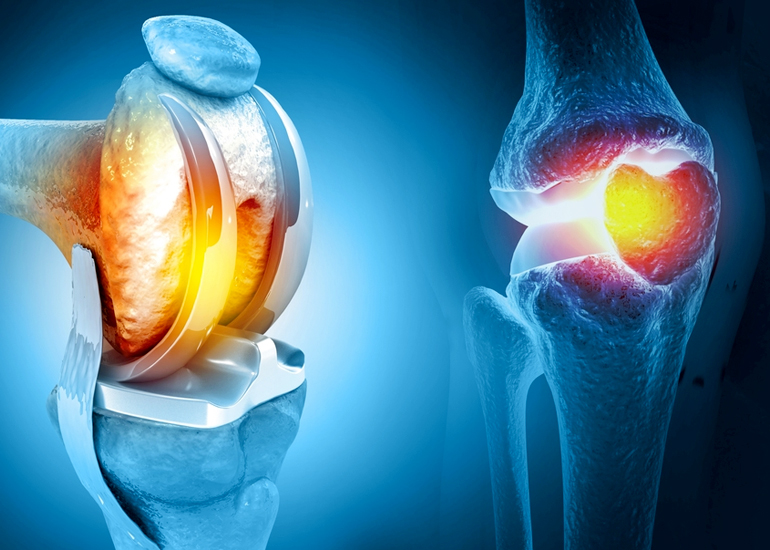

TREATMENT AVAILABLE FOR FOLLOWING DISEASES

Treatment Available